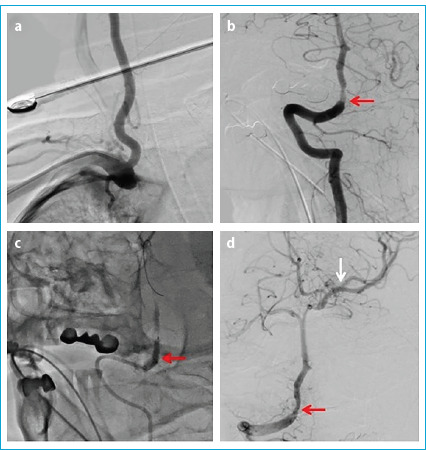

目的:评价有症状的颅内狭窄患者对药物干预反应不充分的血管内治疗的疗效和临床结果。方法:该研究纳入了32例于2021年12月至2023年12月期间因颅内高级别(70%-99%严重程度)动脉粥样硬化性狭窄接受血管内治疗的患者。患者在最近三周内未发生任何急性缺血性或出血性梗死,基线时改良兰金量表评分≤3分,尽管接受了最好的药物治疗,但仍发生过短暂性缺血性发作或非致残性卒中。记录技术和临床成功率、死亡率和并发症发生率。结果:纳入研究的32例患者中,男性占62.5% (n=20),平均年龄66.4±10.09岁。43.8% (n=14)的患者行颅内颈内动脉支架植入术,37.5% (n=12)的患者行硬膜内椎动脉支架植入术,12.5% (n=4)的患者行大脑中动脉支架植入术,6.3% (n=2)的患者行基底动脉支架植入术。技术成功率100%,临床成功率87.5%。术前平均狭窄度为91.7±6.3%,术后残余狭窄度为22.1±4.7%。Neuroform Atlas®支架系统18例(56.3%),Credo®支架8例(25%),冠状动脉球囊可扩张支架4例(12.5%),LVIS®支架系统2例(6.3%)。28例(87.5%)患者在前30天没有任何症状,2例(6.2%)患者发生缺血性卒中,1例(3.1%)患者发生出血性卒中,1例(3.1%)患者死亡。结论:在精心挑选的患者中进行血管内治疗,量身定制的治疗亚型选择,以及一个经验丰富的多学科团队在手术前、手术中和手术后对患者进行监督,有可能为有症状的颅内动脉粥样硬化性狭窄患者提供安全有效的治疗。

Results: Of the 32 patients included in the study, 62.5% (n=20) were male, and the mean age was 66.4±10.09 years. Stenting was performed on the intracranial internal carotid artery in 43.8% (n=14) of the patients, the intradural vertebral artery in 37.5% (n=12), the middle cerebral artery in 12.5% (n=4), and the basilar artery in 6.3% (n=2). The technical success rate was 100%, and the clinical success rate was 87.5%. The mean degree of stenosis before the procedure was 91.7±6.3%, and the degree of residual stenosis after the procedure was 22.1±4.7%. The Neuroform Atlas® stent system was used in 18 cases (56.3%), Credo® stents in eight (25%), coronary balloon-expandable stents in four (12.5%), and the LVIS® stent system in two (6.3%). Twenty-eight (87.5%) patients did not have any symptoms in the first 30 days, while two (6.2%) patients had an ischemic stroke, one (3.1%) patient had a hemorrhagic stroke, and one (3.1%) died.